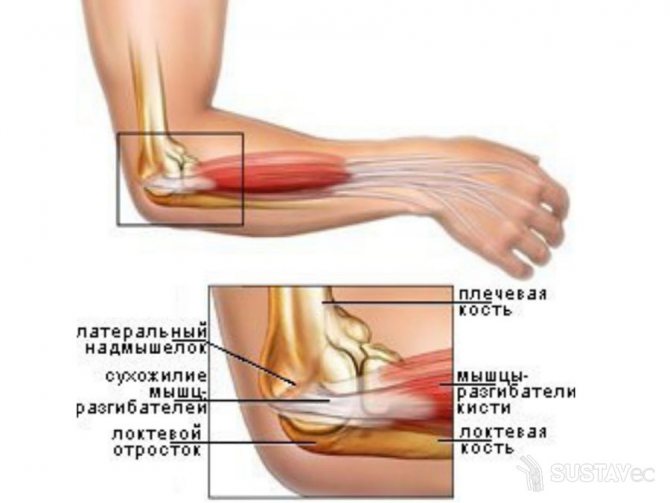

- Эпикондилит – воспаление сухожилий в области надмыщелков плечевой кости. Причиной служат регулярные микротравмы в результате регулярного растяжения. Боль появляется при попытке сжать кисть, пожать руку или взять столовый прибор.

Тендинит

Воспаление сухожилий – тендинит возникает из-за травмирования или воспаления и сопровождается дегенеративными и дистрофическими изменениями. Заболевание чаще встречается у мужчин, что напрямую связано с их профессиональной деятельностью. Именно постоянные и однотипные физические нагрузки приводят к растяжению и травмам сухожилий.

Как правило, чаще болит правая рука, так как на нее приходится основная нагрузка. Воспаление развивается постепенно – сначала чувствуется дискомфорт в моменты напряжения пораженной области. По мере прогрессирования воспаление проявляется все сильнее, и руки от локтя до кисти болят даже при незначительных движениях.

В области пораженной связки наблюдается покраснение и отечность, температура кожного покрова резко повышается, двигательная активность руки снижается. При отсутствии лечения в сухожилиях образуются кальцинаты, и движения сопровождаются характерными звуками – хрустом и щелчками. При пальпации могут прощупываться уплотнения, обусловленные разрастанием фиброзной ткани или отложением солей.

Тендинит локтевого сустава, или локоть теннисиста, характеризуется острой болью, которая усиливается при сгибании-разгибании, вращении или поднятии какого-либо предмета. Действия, связанные с напряжением руки, удаются с большим трудом – даже повернуть кран или тугую дверную ручку становится сложной задачей. Отличительным признаком тендинита является отсутствие боли в состоянии покоя.

В качестве лечебных мероприятий применяются фиксирующие повязки, прием противовоспалительных препаратов, в том числе местного действия, а также ограничение физической активности пораженной конечности.

При этом патологическом состоянии происходит надрыв сухожилий, потом они воспаляются. Еще патология возникнет, если сделать резкое движение (бросок, при поднятиях тяжелых предметов).

Развивается эпикондилит у людей, которые по роду своей деятельности вынуждены часто выполнять сгибание с разгибанием рук в локтевом суставе, руки при такой физической работе перегружаются